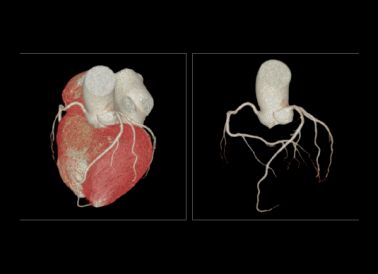

ÔÀíÏÈÈÝ:ÐÄÔà¹ÚÂöCTA¶ÔÐÄÔàºÍ´óѪ¹ÜÆÊ½â½á¹¹µÄÏÔʾÓÅÁ¼£¬¿É¶Ô¹ÚÂö¾ÙÐÐí§Òâ½Ç¶ÈÊӲ죬¸üºÃ¼òÖ±¶¨¹ÚÂö°ß¿éµÄÐÔ×Ó¡£Óë¹Å°å¹ÚÂöÔìÓ°DSAÏà±È£¬¹ÚÂöCTAÄܺܺõÄÏÔʾѪ¹ÜµÄÆô³ÝÇéÐÎ

ÁÙ´²ÓÃ;:¹ÚÐIJ¡¸ßΣÈËȺµÄɸѡ£¬¹ÚÂöÏÁÕˮƽµÄÅжϡ¢¹ÚÂö¸Æ»¯¡¢Ðļ¡ÇÅ¡¢¹ÚÂö»ûÐεÄÕï¶Ï